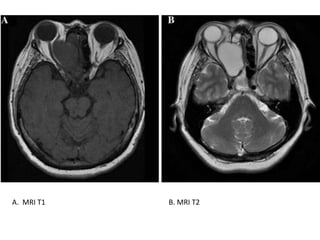

Diagnostika I

MR (izmanto, lai precizētu mukocēles diagnozi un

precīzi noteiktu izplatību)

Signāla intensitāte ir atkarīga no ūdens, gļotu un

proteīnu proporcijas

T1

•  ūdens: hipointenss

•  proteīni: hiperintenss

T2

•  ūdens: hiperintenss

•  proteīni: hipointenss

A. MRI T1 B. MRI T2